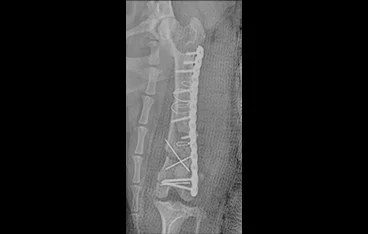

• 골반골절 수술 전

골반골절 수술 후